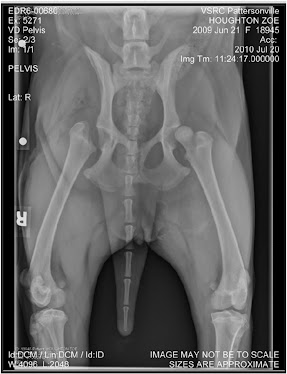

While away in Texas, Josh said Zoe was miserable and wasn't using her leg as much as she had been. I think that it was just Zoe missing me! When I got back she was still miserable and never wanted to go for a walk, barely would walk to use the bathroom. Since Zoe stopped taking the medication she wasn’t using her leg as much as she should have. We should be taking her for at least 3 walks a day but she would get to the end of the road and refuse to walk back!

Because my husband is not a fan of calling anyone I had to call the vet when I got back and ask for suggestions. They recommended we give her the rimadyl that was given to us when she was first diagnosed with hip dysplasia. It is an anti-inflammatory. Since starting with the medicine Zoe has been acting a little more energetic and has some life back in her! She is going for a couple walks a day, when it is not raining and is back to using the stairs.

Zoe is due for her shots tomorrow so she is going in to see the vet and we have been having problems with her getting sores on her back, not sure if it is the food or what but she has about 5-6 sores on her back. Next week we will take her off the anti-inflammatory and hope she doesn’t regress again. She goes back to Dr. Glennon on the 16th of September and we will decide what to do about her other leg.